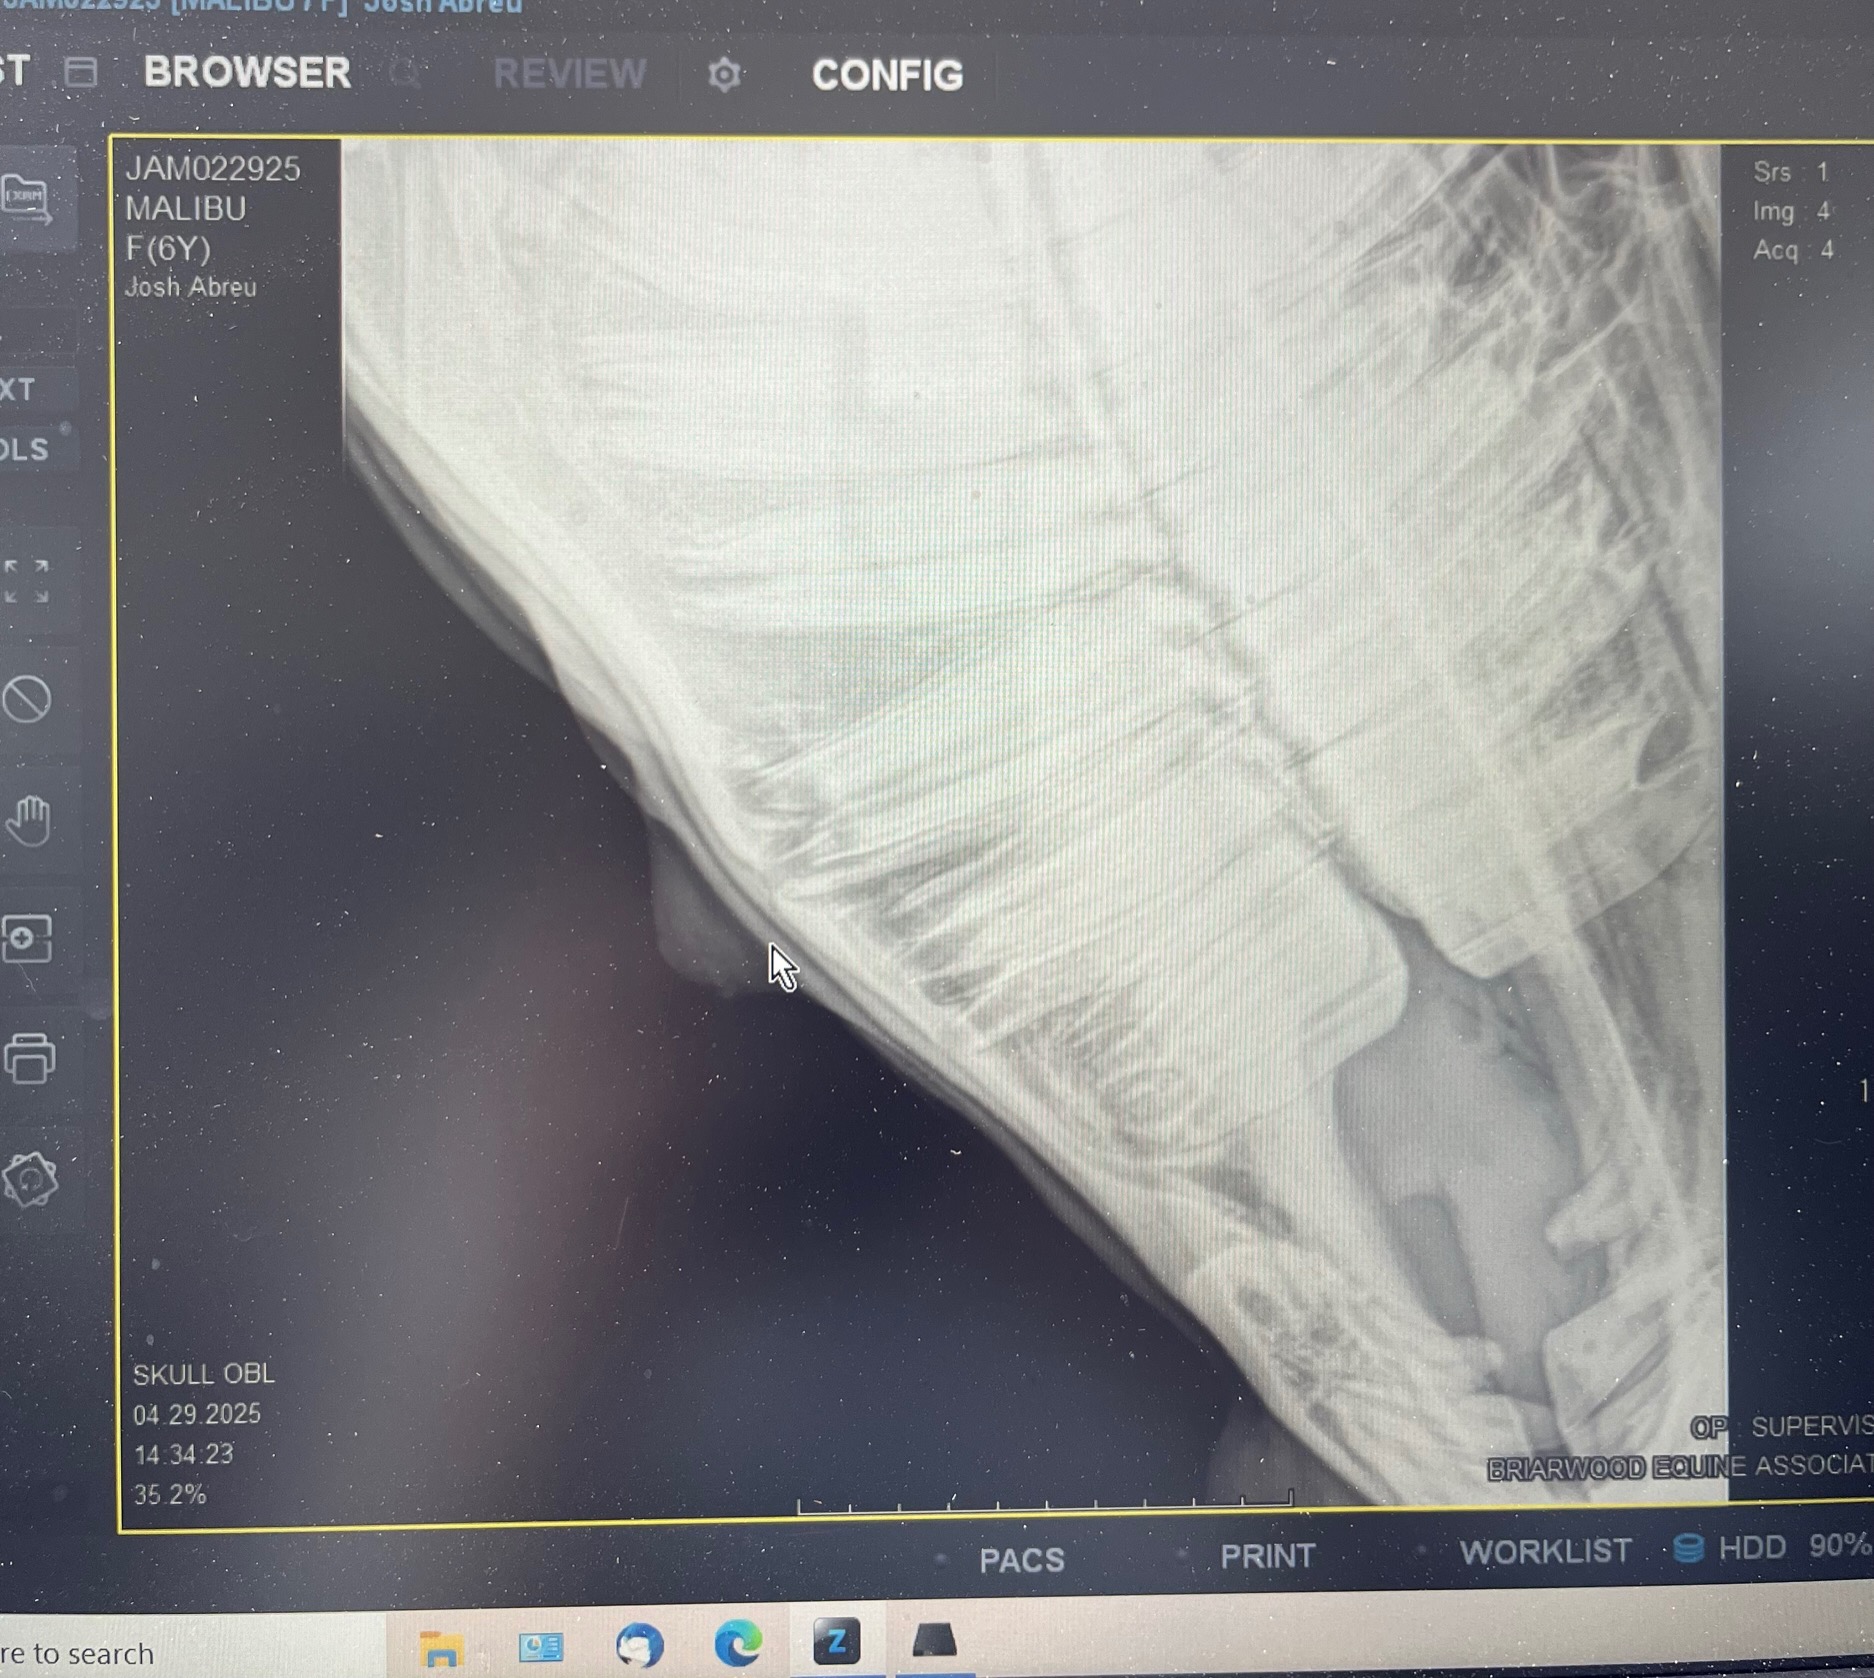

After calling my vet, we learned he needed his teeth floated—a procedure his previous owner hadn’t done. But even after that, something still wasn’t right. Further exams and x-rays showed he had a broken tooth root causing a cyst to form under his jawline. The infection was painful for him, and it became clear he needed surgery.